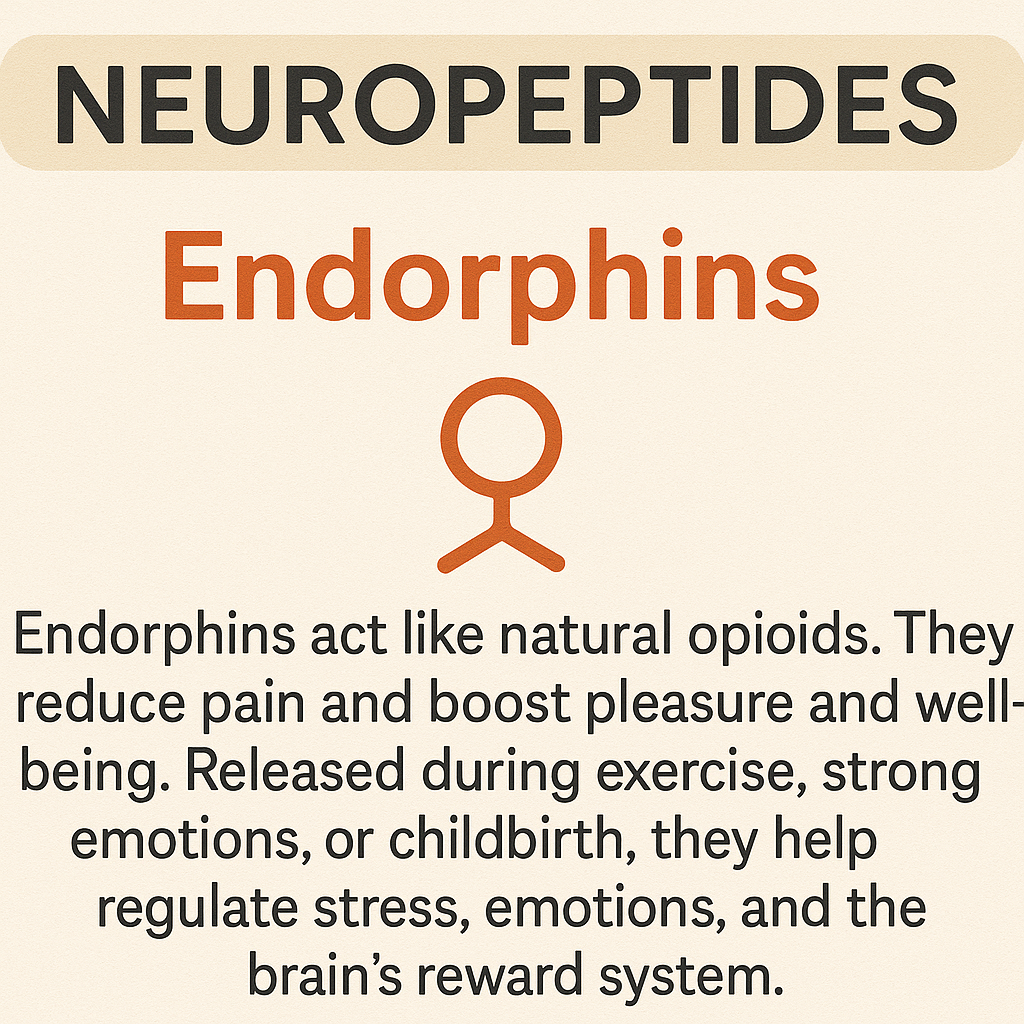

Neurotransmisores

Son sustancias químicas que permiten la comunicación entre las neuronas en el sistema nervioso y piezas fundamentales del engranaje cerebral. Sin ellos, no podríamos movernos, sentir, pensar ni aprender. Actúan como mensajeros que transmiten señales de una célula nerviosa a otra a través de la sinapsis y reforzada por la mielina. Esta función es fundamental para el funcionamiento del cerebro y, en general, del organismo, ya que regula desde procesos automáticos como la respiración o el ritmo cardíaco, hasta funciones complejas como el aprendizaje, la memoria, las emociones y la conducta.

Cuando una neurona se activa, libera neurotransmisores en la sinapsis. Estas moléculas se acoplan a receptores específicos en la neurona siguiente, generando un nuevo impulso eléctrico o modificando la actividad de esa célula. Posteriormente, los neurotransmisores pueden ser degradados, reciclados o reabsorbidos por la neurona original mediante un proceso llamado recaptación.

El equilibrio químico de los neurotransmisores es delicado. Su exceso o déficit puede causar trastornos como ansiedad, depresión, esquizofrenia, Alzheimer o Parkinson.